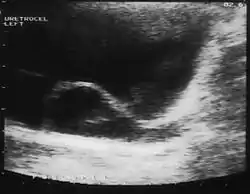

منذ ظهور الموجات فوق الصوتية، يتم تشخيص معظم حالات القيلة الحالبية قبل الولادة. وغالبا ما يتم العثور على حالات الأطفال والكبار بالصدفة، من خلال التصوير التشخيصي الذي يتم إجرائه لأسباب غير ذات صلة.